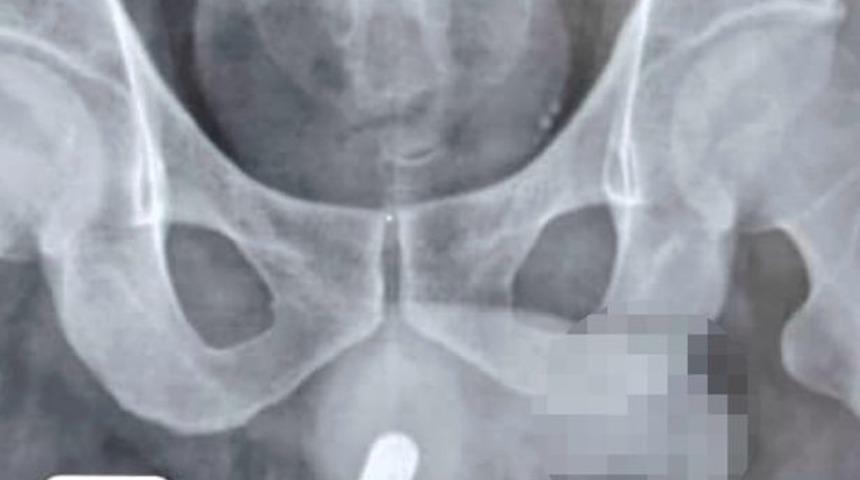

İsmi açıklanmayan 49 yaşındaki bir adam, penisinin içinde 24 saat boyunca bir pil kaldıktan sonra acil bir şekilde ameliyata alındı. Adamın cinsel organında tahribat meydana geldiği söylendi.

Bir adam sosyal medyada gördükten sonra cinsel performansını arttırmak için penisine pil sokmaya karar verdi. Bu tuhaf kararının ardından vücudunda meydana gelen değişiklikler üzerine soluğu hastanede aldı. Obstrüktif üriner semptomlara bağlı olarak acı içinde acil servise giden adamın penisinde 24 saat boyunca duran pil alındı. Beş ay sonra ise tedavi edilen penisinde pilin üriner tıkanıklık komplikasyonlarına yol açması üzerine tekrar hastaneye sevk edildi.

Doktorlar yabancı cisimlerin vücuda girmesiyle birlikte nadir görülen hastalıklara davetiye çıkartabileceğini söyledi. Cinsel organında pil bulunan adama ilişkin raporunda tıbbi ekip, “Pil vücuttan çıkartıldı. Ancak 24 saat pil bulunması üretra ve korpus spongiozumda ciddi ve ilerleyici hasara neden oldu” ifadelerini kullandı.